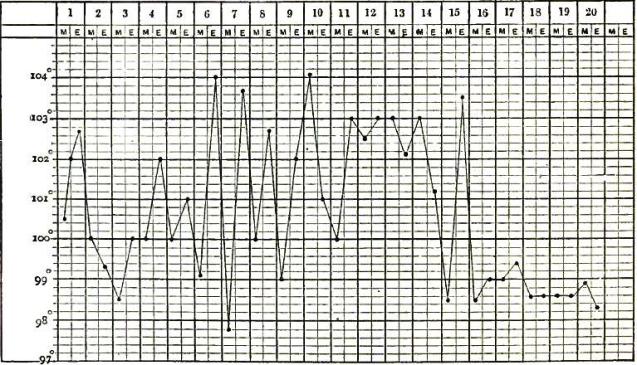

| 12. | CHART OF TYPICAL RANGE OF TEMPERATURE IN TYPHOID FEVER, AFTER WUNDERLICH |

| 21. | TEMPERATURE CHART OF TYPICAL CASE OF RELAPSING FEVER, TERMINATING IN RECOVERY |

| 24. | CHARTS SHOWING THE TEMPERATURE CURVE IN TYPHO-MALARIAL FEVER: PART I., SHOWING PREDOMINANCE OF TYPHOIDAL ELEMENT; PART II., SHOWING PREDOMINANCE OF MALARIAL ELEMENT |